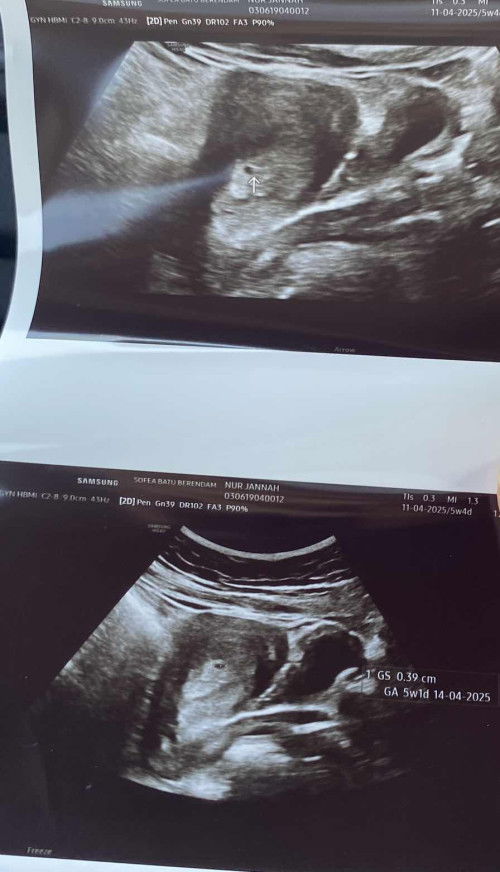

Hi mommies! Sorry gambar kotor. Saya pregnant 5w4d and this is my 2nd pregnancy. The 1st one gugur. Pagi selasa saya pergi scan kat klinik and nampak dah kantung. And dr memang dah confirm memang i pregnant. Start tengahari turun darah and perut start sakit mcm first gugur sebelum ni. Pergi hospital dr buat upt siap scan ikut bawah tapi tak nampak apa2 langsung so dr cakap saya overexcited sebab pregnancy yg before this tak menjadi and assume it’s just a period cramp and delayed menstruation. So dr pun discharge saya. Balik dlm keadaan perut still sakit mcm nk pitam dah tapi terpaksa jalan. Sampai rumah masuk tandas ada keluar ketulan merah mcm dalam gambar tu. Lepas dari tu terus hilang rasa sakit tadi means tanda2 tu semua memang betul2 rasa tanda2 keguguran mcm masa 1st pregnancy tu. Kalau saya tak pregnant then ketulan besar ni apa ya? Sebab tak pernah saya period keluar ketulan besar mcmtu.

Baca lagisy gugur 4x yg last cmni lah ge hospital semua ckp sy tak mengandung buat urin pon negatif sampai hantar urin kt makmal pon jawapan yg sama. balik rumah mlm tu terus keluar cmtu lah tp lagi terang. bln depan tu terus cek memang mengandung ni dah 12 mnggu dah. tu gambar bln 5 haritu yg doc ckp sy tak mengandung